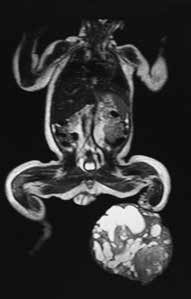

Anamnese und Diagnose (Abb. 7a–c)

In der Woche vor dem Geburtstermin kommt im Rahmen einer sonographischen Untersuchung des Patienten der Verdacht auf ein Steißbeinteratom der Mutter mit Differentialdiagnose Plazentatumor (Rhabdomyosarkom) auf. Perinatal erweist sich dies jedoch als Weichteilsarkom des Unterschenkels des Patienten. In der Folge wird der Patient an seinem zweiten Lebenstag linksseitig transtibial amputiert (Abb. 7c). Im weiteren Verlauf erhält er teilstationär Chemotherapie.